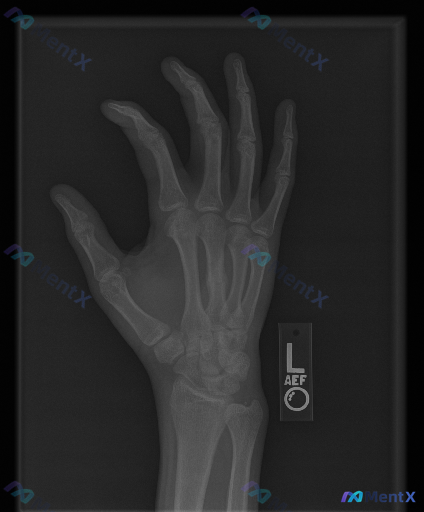

左手正位X光片报告基本正常,但提示存在异常,这种情况更优先考虑哪种方向?

整理到一组影像资料和配套的分析背景,想和大家讨论下这种情况的思路: - 影像来源:左手正位X光片 - 常规阅片所见: - 各腕骨、掌骨、指骨骨皮质轮廓尚完整,未见明显骨折线、脱位或半脱位; - 骨密度、关节间隙未见明显异常; - 关节面、软骨下骨、软组织影也未见明确的典型异常改变(如骨赘、弥漫肿胀、...

整理到一个影像相关的病例情况,想和大家讨论下判断思路: - 影像资料:左手正位X光片 - 读片所见:各指骨、掌骨、腕骨皮质连续,未见明确骨折线、脱位或半脱位;骨小梁清晰,密度均匀,无明显骨质破坏、骨膜反应或异常钙化;各关节间隙对称、宽度正常,关节面光滑,无明显骨赘或侵蚀;周围软组织轮廓自然,未见明显...

整理到一组左手正位X光片的影像评估资料,同时结合了临床场景的提示,想跟大家讨论一下这种情况的判断思路。 影像所见 - 骨皮质连续性:指骨、掌骨及腕骨骨皮质连续,未见明确骨折线、中断或台阶征;第一掌骨基底、第五掌骨颈区域也无异常 - 骨髓腔密度:骨小梁结构清晰,纹理分布均匀,未见局灶性骨质破坏、虫蚀样...